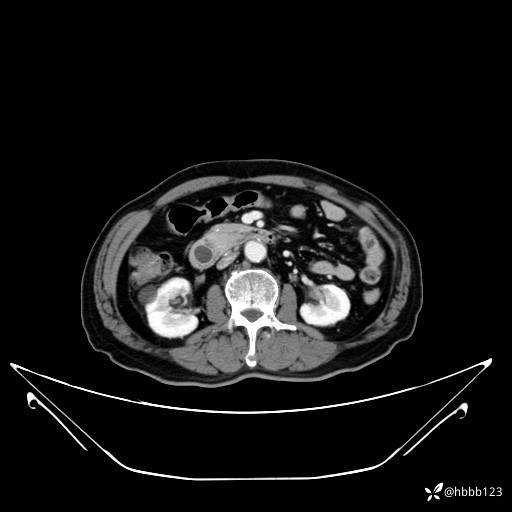

动脉期: